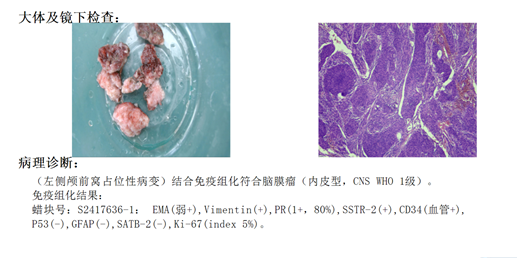

前颅窝底脑膜瘤常起源于前颅底筛骨筛板处的硬膜,瘤体多为双侧生长,少数为偏侧生长,女性稍多于男性。肿瘤可累及鸡冠和蝶骨平台的任何区域,是前颅窝肿瘤中最多见的一种。因为肿瘤位于前颅窝底,额叶在功能上属于“哑区”,患者就诊发现肿瘤时瘤体多已巨大。主要症状可有颅内压增高症状、视力减退、癫痫以及精神症状等。该患者主因“左眼失明10个月,头痛3个月”就诊。术中采用双额冠状开颅,左侧为主,由于肿瘤体积巨大,术中切除少许薄层额叶脑组织,边离断基底、边瘤内减压,分块切除肿瘤,最终探查肿瘤基底主要位于鸡冠、筛板、蝶骨平台、鞍结节、前床突处硬膜,术中见肿瘤供血主要来源于前颅窝底硬膜及大脑前动脉分支,术中仔细辨认供血动脉、过路血管,大脑前动脉及其分支保护完好,术中见视神经、视交叉受压明显,尤其是左侧视神经已缺血苍白,最终达Simpson II级切除。术者体会,该患者术前行多模态重建,可见瘤表数条粗大的静脉,术中切莫过早离断肿瘤的引流静脉,以防因引流不畅致瘤体肿胀出血;术前行多模态重建,利于鉴别供血动脉、过路血管,早期离断供血动脉更利于肿瘤切除;该类肿瘤基底一般较为广泛,不能盲目离断基底,尤其是近鞍结节处,可以于中线处离断基底,进入第一间隙后向两侧探查并保护视神经,待充分缩小瘤体看清楚毗邻的血管神经后再将其完全切除;术毕做好多层颅底重建以防脑脊液漏。另外,该患者术前左眼失明已达10个月,术后第1天即有光感,术后1月复查左眼视力可达50cm内数指,这在临床中非常少见,对于此类病人,不要轻易放弃挽救视力的任何机会。